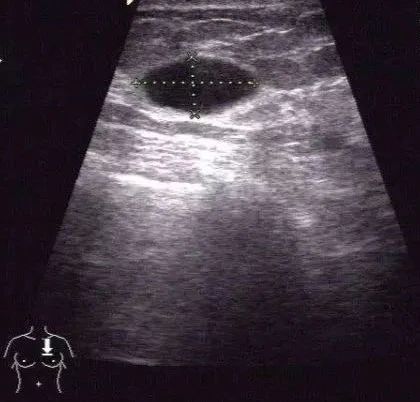

囊肿可单发,亦可多发。平时我们自己看不到囊肿,也没有任何感觉。

大一些的囊肿患者可能可以自己摸到,张力比较大的囊肿比较好摸到,较软的囊肿很难摸到,需要全自动乳腺超声波检查设备检查发现。